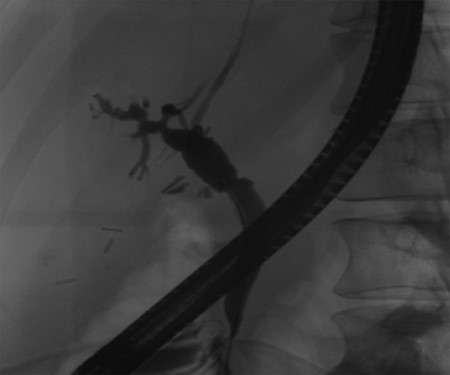

Follow-up ERCP 4 weeks later displaying resolution of all abnormalities.

A 35-year-old female with a medical history significant for acute biliary pancreatitis status post laparoscopic cholecystectomy, presented to the surgery clinic as a new consult for a large cystic liver mass with increasing abdominal pain for 2 weeks. Patient reported suffering from severe pain in right chest, shoulder and diffuse abdominally that worsened with standing. Patient complained of inability to inspire due to pain and a 10-pound weight gain over 2 months. She confirmed decreased appetite especially with solids, nausea and emesis, alternating constipation and diarrhea, bruising, and pruritus at night. Computed tomography (CT) scan demonstrated a peripherally septated 10 x 7 cm cystic mass in the liver with intrahepatic biliary dilation (Fig. 1). The patient was referred for endoscopic retrograde cholangiopancreatography (ERCP) to establish preoperative biliary anatomy and was found to have moderate compression of the common hepatic duct managed with a right hepatic biliary endoprosthesis (Fig. 2); no obvious communication of the biliary tree with the cystic lesion was seen. Patient symptoms persisted despite optimizing with a protein-rich liquid diet; thus, the decision was made to proceed with the surgical plan for an open partial central hepatectomy. The patient was taken to the operative theater. After induction of general anesthetic, an upper midline incision was made. Inspection of the abdomen and liver showed no metastatic lesions grossly or with ultrasonographic imaging. The cyst was visible upon entry into the abdomen with no solid component to the mass in proximity to the cystic neoplasm. The second portion of the duodenum was adherent to the cyst with inflammatory adhesions and was quite boggy. A partial central hepatectomy was performed; a 3 mm biliary duct was found communicating to the cyst only with no drainage to the minimal liver parenchyma that was removed (Fig. 3). The cyst was resected en-bloc and was sent for permanent section (Fig. 4), which diagnosed the tumor as a low-grade mucinous cystic neoplasm measuring 8.5 × 7.2 × 6.4 cm. Microscopy revealed a smooth-walled, multiloculated cyst filled with a yellow-golden, semi-transparent and mucinous fluid (Fig. 5a–c). The cyst was lined by a mucinous epithelium with ovarian-type stroma. No high-grade dysplasia or malignancy was identified. The postoperative course was uneventful, and the patient was discharged on postoperative day 6. At the 4-week postoperative visit, the patient was healing well with some incisional soreness; patient was seen for removal of her biliary endoprosthesis, and ERCP found left sided intrahepatic duct biliary dilatation including a small biliary fistula from the left system (Fig. 6) with the appearance of torque on the extrahepatic biliary tree. A biliary endoprosthesis was left in place, and the patient returned for repeat ERCP 4 weeks later with resolution of all findings (Fig. 7). At present, patient remains alive with no signs of recurrence.